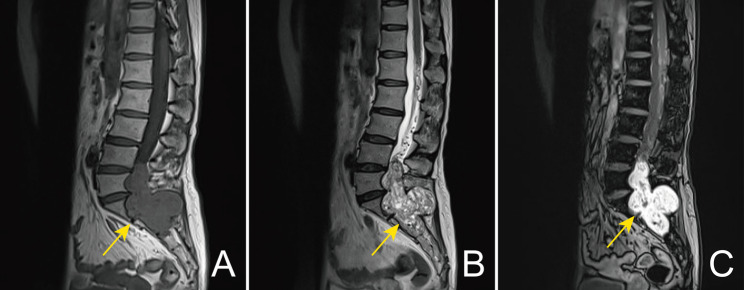

Solitary fibrous tumor (SFT) is a fibroblastic tumor characterized by a prominent staghorn vasculature and collagen deposition. However, little is known about SFTs with alveolar structures. Herein, we present a case of an alveolar pattern SFT in a 55-year-old woman. The tumor was present in the lumbosacral spinal canal and showed an alveolar architecture composed of ovoid to spindle-shaped cells. Immunohistochemical examination showed that the tumor cells were positive for STAT6 (nuclear expression), CD34, CD99, and Bcl-2, but negative for cytokeratins (CK-pan and AE1/AE3), EMA, GFAP, CD31, progesterone receptor, S-100 protein, and smooth muscle actin. Furthermore, NAB2::STAT6 fusion was detected using DNA-based next-generation sequencing, which established the diagnosis of SFT at a molecular level. The present case expands the morphological categories of SFT.